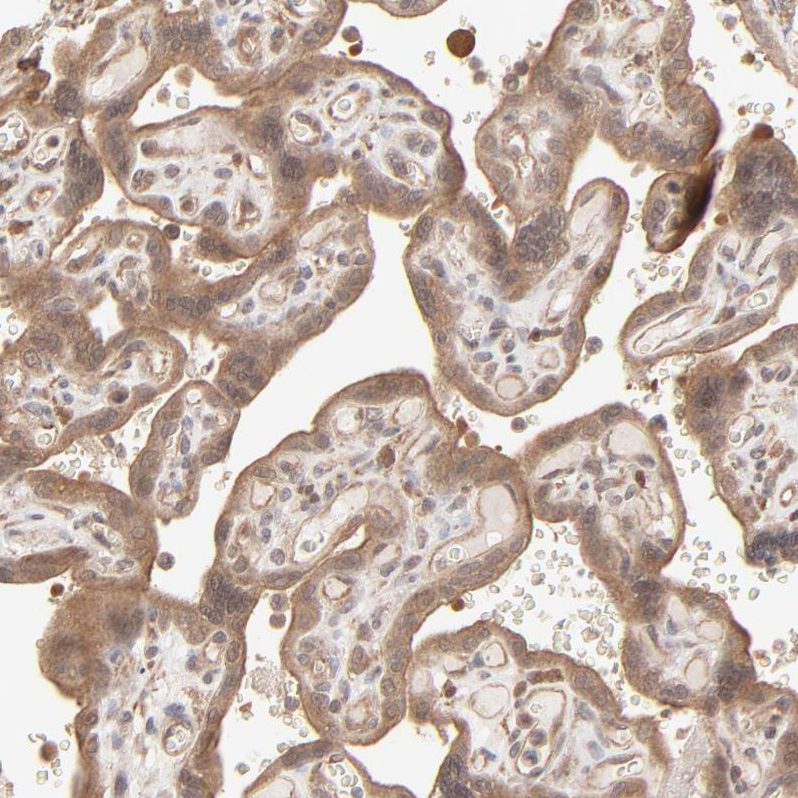

Immunohistochemical staining of human testis shows strong cytoplasmic positivity in cells in seminiferous ducts.